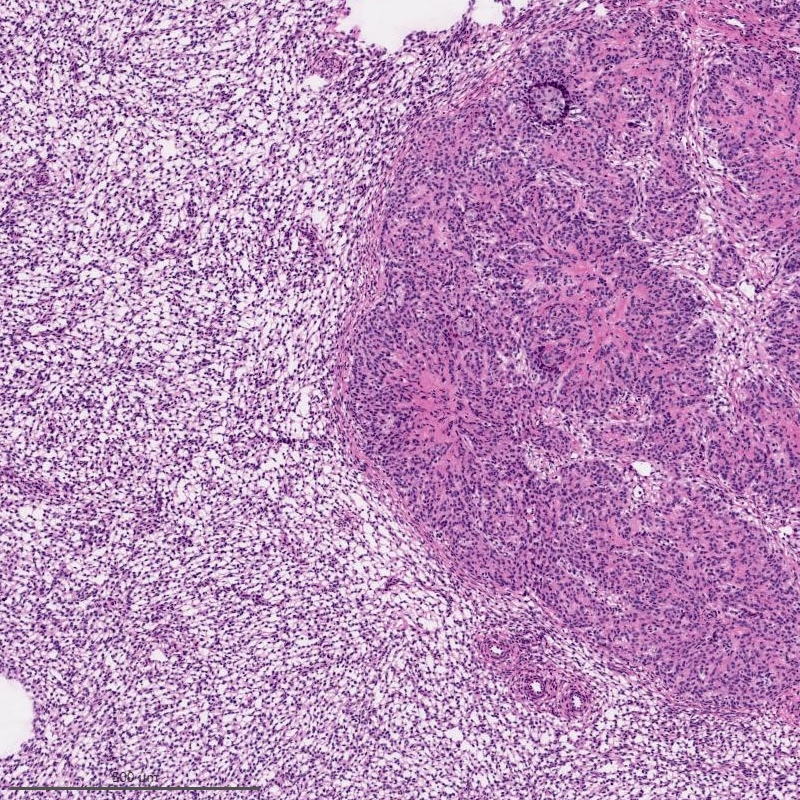

Microscopic (histologic) description

- Irregular cellular islands, forming permeative tongue-like pattern of myometrial invasion with frequent vascular invasion

- Monotonous oval to spindle cells with minimal cytologic atypia, vesicular chromatin and scant cytoplasm

- Mitotic count is usually low (< 5/10 high power fields), necrosis is usually absent

- Tumor cells may whorl around delicate arteriolar type vessels, reminiscent of proliferative phase endometrial stroma

- May have admixed collagen bands / plaques and foamy histiocytes

- May have smooth muscle differentiation, particularly in a starburst morphology, with collagen bands radiating towards the periphery of the nodule

- Other reported types of differentiation: fibromyxoid / fibrous, sex cord-like, epithelioid, rhabdoid, endometrioid glands, pseudopapillae, clear cells, bizarre cells, adipose tissue (Mod Pathol 2016;29:S92)

Microscopic (histologic) images

Contributed by Elizabeth Kertowidjojo, M.D., Ph.D., M.P.H. and Ayse Ayhan, M.D., Ph.D.